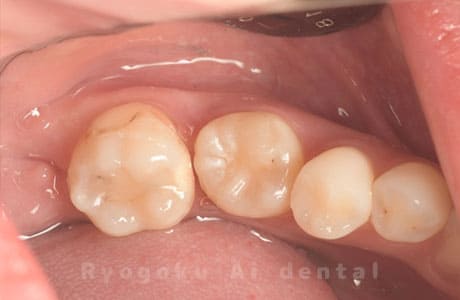

Case27

-

重度カリエス

歯牙移植咬合面術前 -

移植する親知らず

歯牙移植術直後咬合面

歯牙移植術後咬合面

歯牙移植術前側面

歯牙移植術中側面

歯牙移植術後側面

- 原因

- 重度カリエス

- 治療内容

- 自家歯牙移植、部分矯正

- 治療費用

- 220,000円(移植費用)

110,000円(部分矯正費用)

虫歯が大きく、保存不可能となった歯を上の親知らずと交換する自家歯牙移植を行いました。移植歯が小ぶりであったため、部分矯正を行い問題なく噛み合い、経過良好です。